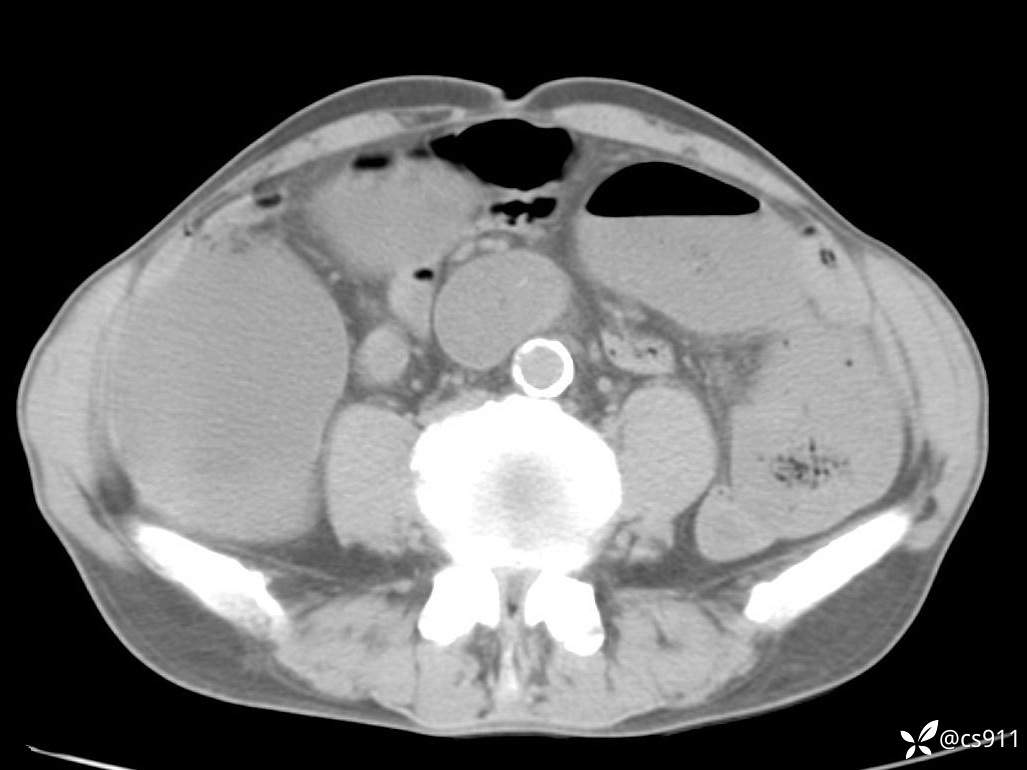

急腹症之急诊CT,原因?答案公布

男,77岁,腹痛、腹胀伴恶心呕吐1天。呕吐胃内容物,非喷射性呕吐,有咖啡色样胃内容物,诉有胃穿孔病史。查体:全腹平,下腹部压痛,全腹无反跳痛,叩诊呈浊音,移动性浊音阴性,肠鸣音减弱,1-2次/分。肛检:直肠未扪及明显肿物,可触及大量粪块。

T 36.6℃ P 80次/分 R 26次/分 BP 100/60mmHg

白细胞(WBC) H 14.55 10e9/L 4-10

中性粒细胞百分率(NEUT%) H 85.7 % 40-75

血淀粉酶(AMY) HH 1859 U/L 35-135

癌胚抗原(CEA) H 27.44 ng/ml 0-5

呕吐物 潜血试验 * 阳性 阴性

患者轮椅入室检查神志清楚, 能配合摆位和呼吸